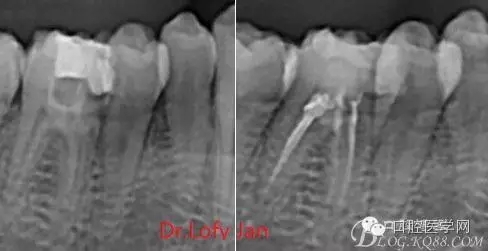

前言:自己做的一些曲面斷層片在未試尖根管治療中的病例整理,發(fā)現(xiàn)問題很多包括自身的,技術(shù)的,還有設(shè)備的問題,予以總結(jié)整理并期待進(jìn)一步提高。

根管治療術(shù)是牙體牙髓疾病治療中最復(fù)雜和最關(guān)鍵的治療項(xiàng)目。根管充填材料抵達(dá)根尖、并能嚴(yán)密堵塞根尖孔,是確保根管治療效果的關(guān)鍵指標(biāo)。為了保證根管充填到位,醫(yī)生需要在術(shù)前照牙片以了解牙根根管的數(shù)量、彎曲程度和長度,在術(shù)中有時(shí)需要插針照牙片來精確測量根管長度,術(shù)后必須照牙片以確定是否根管充填到位,如果欠填或超填,就需要重新充填、重新照牙片確認(rèn),直到根管充填到位。所以,在患者接受根管治療時(shí)有時(shí)會反復(fù)照牙片。

病例分析:曲面斷層片在x線輔助診斷與檢查中目前大多數(shù)文獻(xiàn)和著作都建議只能作為初診拍片檢查手段,不能作為終末疾病的確診與手術(shù)療效的評價(jià)指標(biāo),臨床大部分中小型門診都因?yàn)樵O(shè)備不齊全導(dǎo)致信息偏差很大。